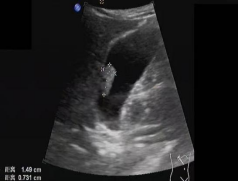

首选检查为超声检查,该检查无创、方便易行、廉价,对息肉的形态、血流有很好的判断,尤其对胆囊胆固醇沉积症、胆囊腺肌症等有独特的影像显示,是常规体检、随访的必备检查。

• 最大径>10mm的胆囊息肉,应行胆囊切除术;

• 如超声检查探及血流信号,则肿瘤性息肉可能性大,不论息肉大小,应及时行胆囊切除术。